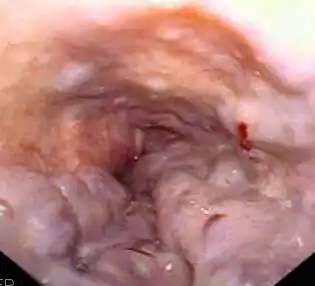

![]() Gastroscopia en la que se observan varices esofágicas. | ||

El diagnóstico se establece por medio de una esofagogastroduodenoscopia, la cual debe ser realizada en todo paciente con hemorragias idiopáticas, cirrosis o esplenomegalia y con carácter de urgencia si presentan sangrado digestivo masivo. Las varices se presentan de color azul, redondeadas y compresibles, haciendo prominencia en la mucosa del esófago. La ventaja de este diagnóstico directo es poder saber su posición, tamaño y otros signos como manchas rojas brillantes que indiquen un inminente sangrado o coágulos de sangre donde haya existido una hemorragia.